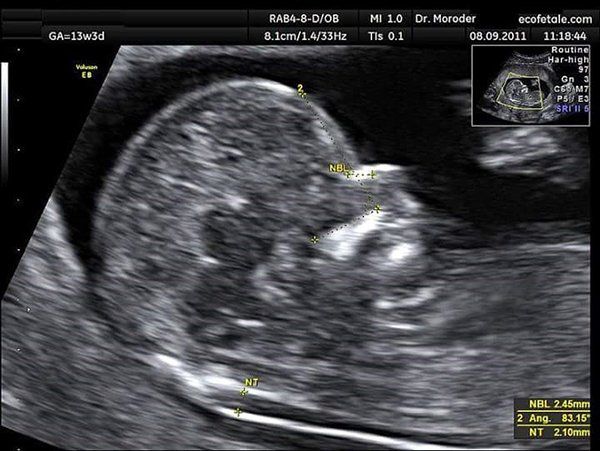

Entre semana 11 a la 14:

TRANSLUCENCIA NUCAL _(TN)

Mediante este estudio(medición del pliegue transnucal) intentamos evaluar estructuras anatómicas muy precisas que nos sugieren presencia de anomalías cromosómicas, por ejemplo el síndrome de Down.

Además de la TN, complementamos este estudio con otros signos ecográficos útiles para este fin como son la evaluación del Hueso nasal (HN), Ductus Venoso, Angulo maxilofacial y Regurgitación tricúspidea.